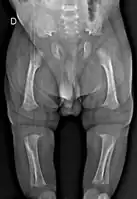

Radiologic findings

A skeletal survey is useful to confirm the diagnosis of achondroplasia. The skull is large, with a narrow foramen magnum, and relatively small skull base. The vertebral bodies are short and flattened with relatively large intervertebral disk height, and there is congenitally narrowed spinal canal. The iliac wings are small and squared, with a narrow sciatic notch and horizontal acetabular roof.[15][16] The tubular bones are short and thick with metaphyseal cupping and flaring and irregular growth plates.[15] Fibular overgrowth is present. The hand is broad with short metacarpals and phalanges, and a trident configuration. The ribs are short with cupped anterior ends.[15] If the radiographic features are not classic, a search for a different diagnosis should be entertained. Because of the extremely deformed bone structure, people with achondroplasia are often "double jointed". The diagnosis can be made by fetal ultrasound by progressive discordance between the femur length and biparietal diameter by age. The trident hand configuration can be seen if the fingers are fully extended.

Another distinct characteristic of the syndrome is thoracolumbar gibbus in infancy.